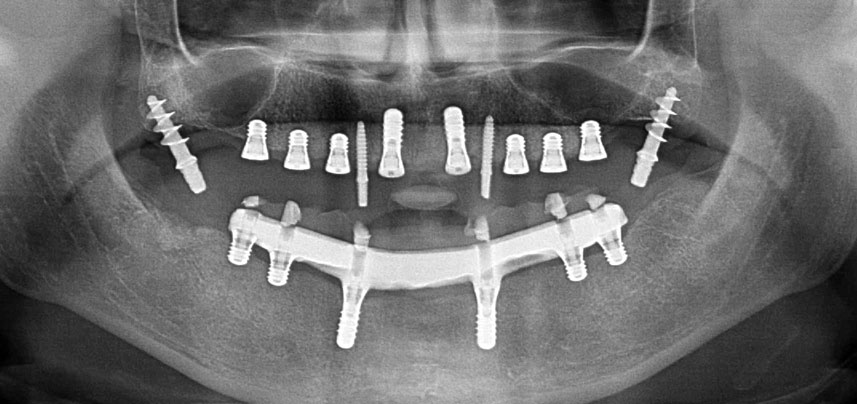

Tres años después, llegó el momento de colocar una prótesis del mismo tipo en el maxilar superior. Basándose en una planificación mediante tomografía computarizada de haz cónico (CBCT, por sus siglas en inglés), se evitó la necesidad de realizar una elevación del seno utilizando implantes cortos, mientras que una plantilla quirúrgica sirvió para transferir las posiciones planificadas al borde alveolar (figuras 1 y 2).

Debido al hueso relativamente duro (D2) existente en el sector anterior, los sitios de los implantes largos de 10 mm de las posiciones 11 y 21 se finalizaron con una fresa rotatoria de 4 mm de diámetro, en combinación con un contra-ángulo quirúrgico WS-75 L de W&H, el motor de implantes Implantmed de W&H y el módulo opcional Osstell ISQ de W&H. En cambio, debido a la existencia de hueso blando, los sitios posteriores se prepararon hasta un diámetro final de 3 mm utilizando el inserto Piezomed I3P. Por último, los implantes se colocaron a nivel crestal para su osteointegración durante tres meses (figuras 6-10). La prótesis existente se mantuvo sobre cuatro implantes provisionales (figura 8).